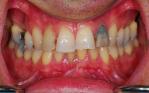

Replacement of all four failing lower front teeth with an implant bridge, some whitening, composite bondings and one new crown on an upper lateral incisor